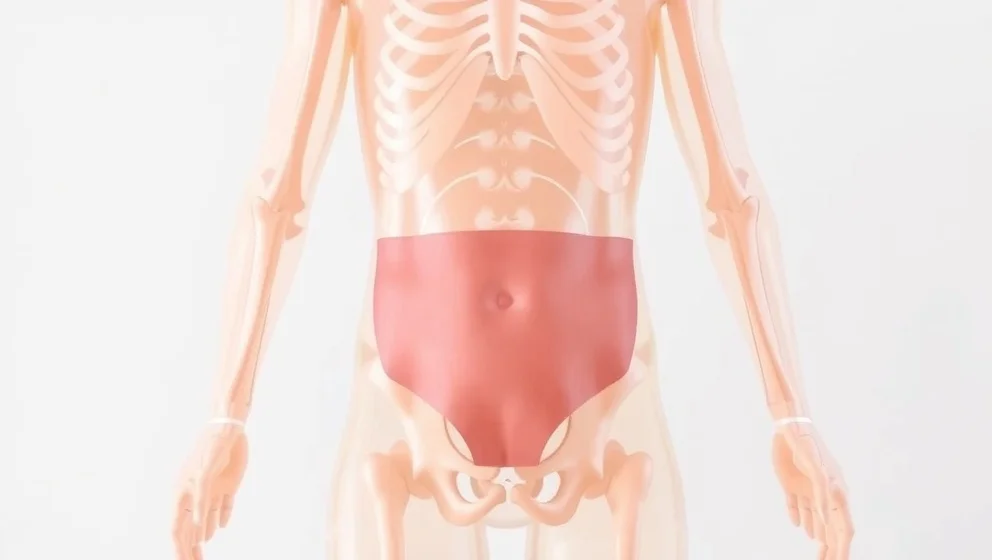

Buken ligger mellan revbenen och bäckenet. Du lär dig var de viktiga organen sitter och hur magen, levern och tarmen fungerar tillsammans.

Gallblåsan sitter gömt under levern på höger sida av magen. Du får veta vad gallblåsan gör och varför den är viktig för matsmältningen.

Levern sitter under höger revben och väger ungefär 1,5 kilo. Den är kroppens största inre organ och gör många viktiga jobb för att hålla dig frisk.

Njurarna sitter djupt inne i magen, på varje sida av ryggraden. Du får veta exakt var de ligger och vad de gör.

Blindtarmen sitter i nedre höger delen av magen. Du får veta exakt var den ligger och varför den kan bli inflammerad.